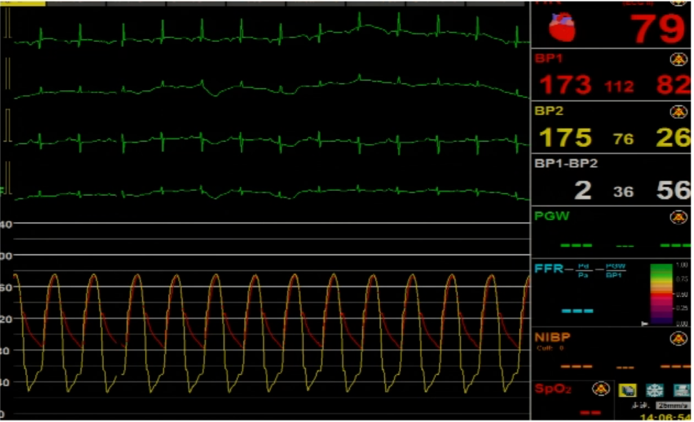

植入前后跨瓣压差

植入前压差63mmHg,植入后压差2mmHg

植入前压差67mmHg,植入后压差2mmHg